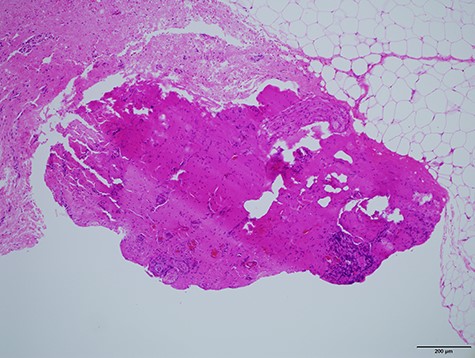

In the histological report, only fibrous scar was found without a sign of fistula or epithelial cells (Fig. 4).

Histological specimen showing the string-like structure. No epithelial cells were observed by the pathologists.